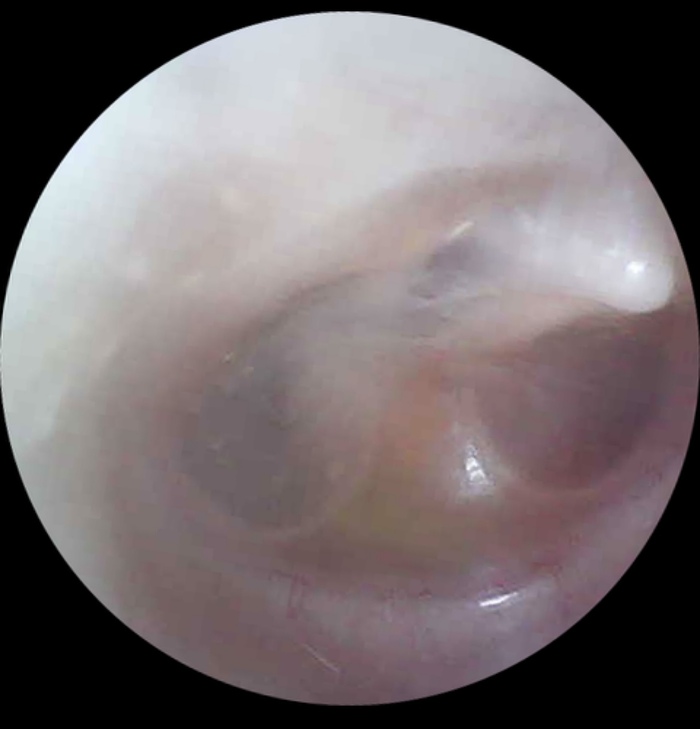

Пациентку при обращении на прием беспокоило не только затруднение носового дыхания, а также ощущение заложенности в правом ухе, что собственно и привело на прием. В рамках обычного ЛОР-осмотра, при отоскопии барабанная перепонка была неподвижна при проведении проб Тойнби и Вальсальвы. Сочетание затруднения носового дыхания, в сочетании отсутствия привычной подвижности барабанной перепонки в большинстве случаев является проявлением состояния, которое мы называем дисфункция слуховой трубы.

Было назначено консервативное лечение с использованием интраназальных глюкокортикостероидов (ИГКС) однако лечение оказалось неэффективным, в связи с чем пациентке была выполнена коррекция внутриносовых структур, включающая в себя септопластику, двустороннюю вазотомию и латероконхопексию.

Через 1 месяц после операции на контрольном осмотре мы выявили полное заживление, а функция слуховой трубы была восстановлена, в связи с чем ощущение заложенности в правом ухе пациентку больше не беспокоило. Кроме того, пациентка отметила значимое улучшение носового дыхания.

P.S. Дисфункцию подтверждаем не только визуально, но путем проведения импедансометрии с ETF (EustachianTube Function). В послеоперационном периоде рутинно не исследуем, только если сохраняются жалобы